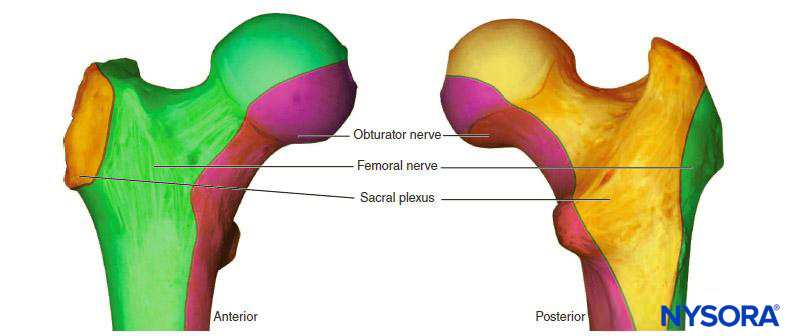

In the absence of rare complications such as pneumothorax, any alterations in respiratory mechanics seen with brachial plexus block are due primarily to phrenic nerve block and hemidiaphragmatic paralysis (Figure 1). This has been shown to occur in 100% of patients receiving interscalene block when performed without ultrasound guidance and using between 34 and 52 mL of local anesthetic. When diaphragmatic paresis occurs, there is an associated 27% reduction in both FVC and FEV1. While the clinical significance of this reduction in healthy patients is not entirely clear, it may be useful to risk-stratify patients about to undergo interscalene blocks as one would a patient undergoing lung resection. In other words, ask the question, “Will this patient tolerate a periopera-tive FEV1 reduction of 27%?”

The risk of phrenic nerve block decreases as one moves more distally along the plexus. The axillary approach to the brachial plexus has no effect on diaphragm function and presents a good choice for those patients with marginal pulmonary reserve (ie, cannot tolerate a 27% reduction in lung function). On the other hand, the supraclavicular block has been traditionally associated with a 50%–67% incidence of hemidiaphragmatic paralysis, although recent studies have shown that with ultrasound guidance the incidence can be as low as zero. The infraclavicular approach is probably suffi-ciently distant from the course of the phrenic nerve so as to spare the diaphragm,40,41 although there are case reports of phrenic nerve involvement.42,43 These discrepancies probably relate to the dif-ferent approaches to the infraclavicular block—for instance the “coracoid block” is performed with a relatively lateral or distal puncture site, whereas the vertical infraclavicular block begins at a more medial location. There may also be some anatomic variations in the course of the phrenic nerve, such as an acces-sory phrenic nerve, which would make it more susceptible to block at more distal levels of the brachial plexus.44